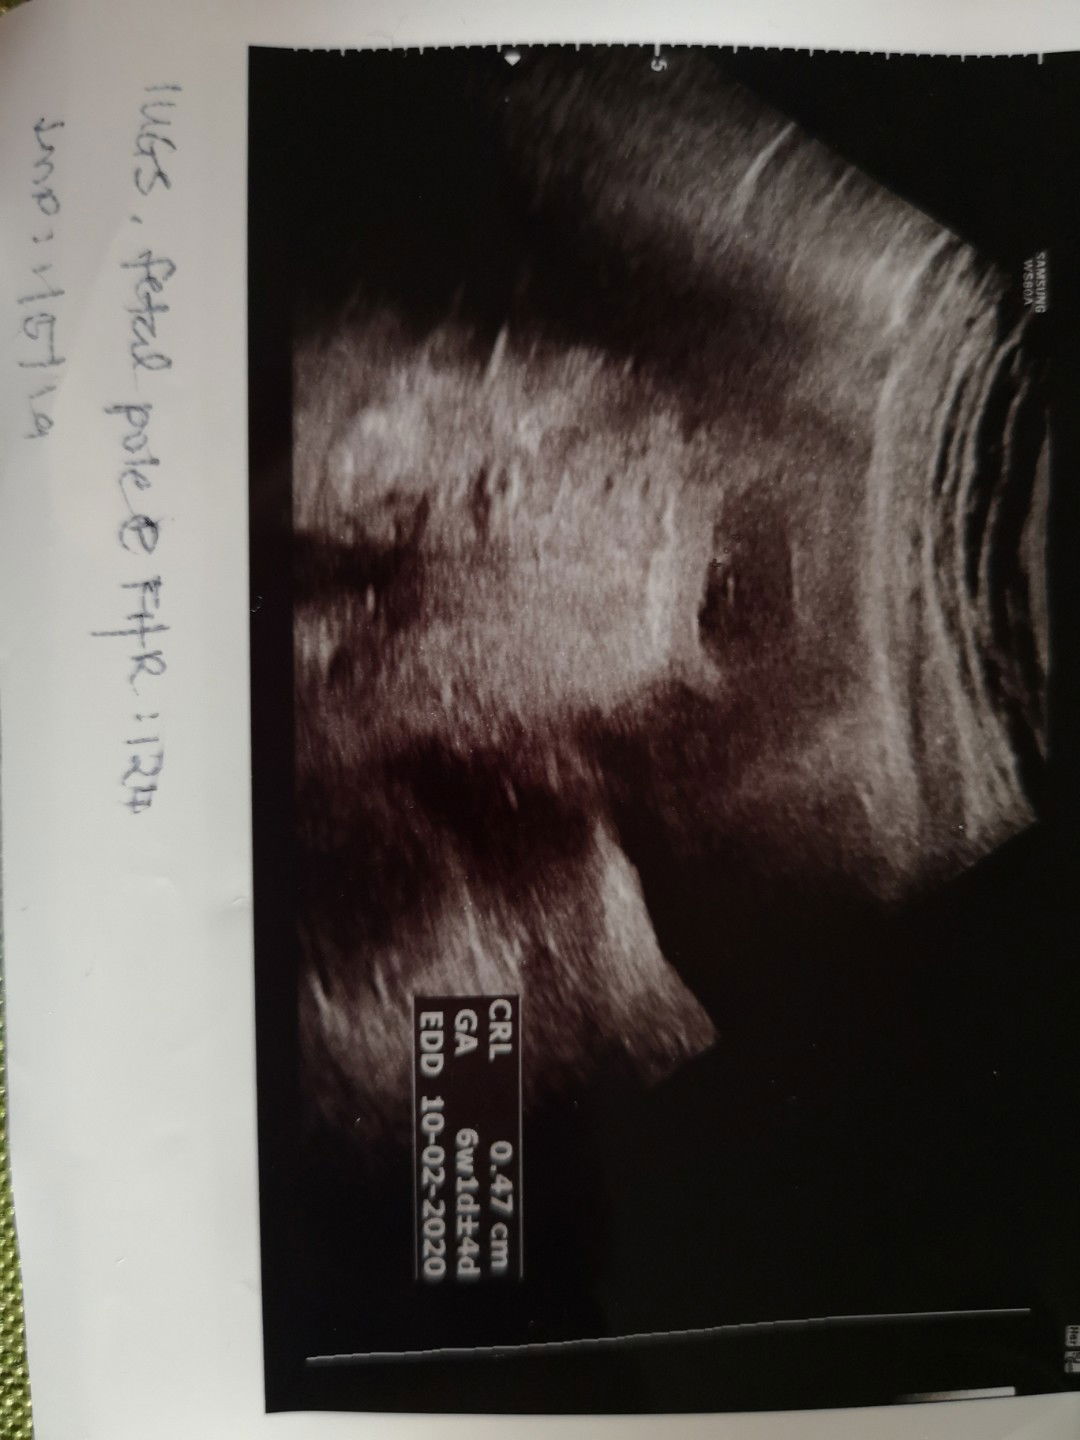

Repeat Scan 7weeks = 6weeks

Alhamdulillah. Haritu Kes Scan 6weeks Baru nampak kantung. Then tunggu lagi seminggu 7weeks, pegi scan lagi sekali. Alhamdulillah, kali ni doktor dapat scan kantung dan janin. Dah dapat dengar bunyi jantung. Roughly doktor kata baru dalam 6weeks. Meaning, ovulation mgkin lewat. Btw, Alhamdulillah. Jantung Baby 124beats. Sebak dengar bunyi jantung dia. Walaupun 2nd baby, tapi teruja tu tetap ada ?